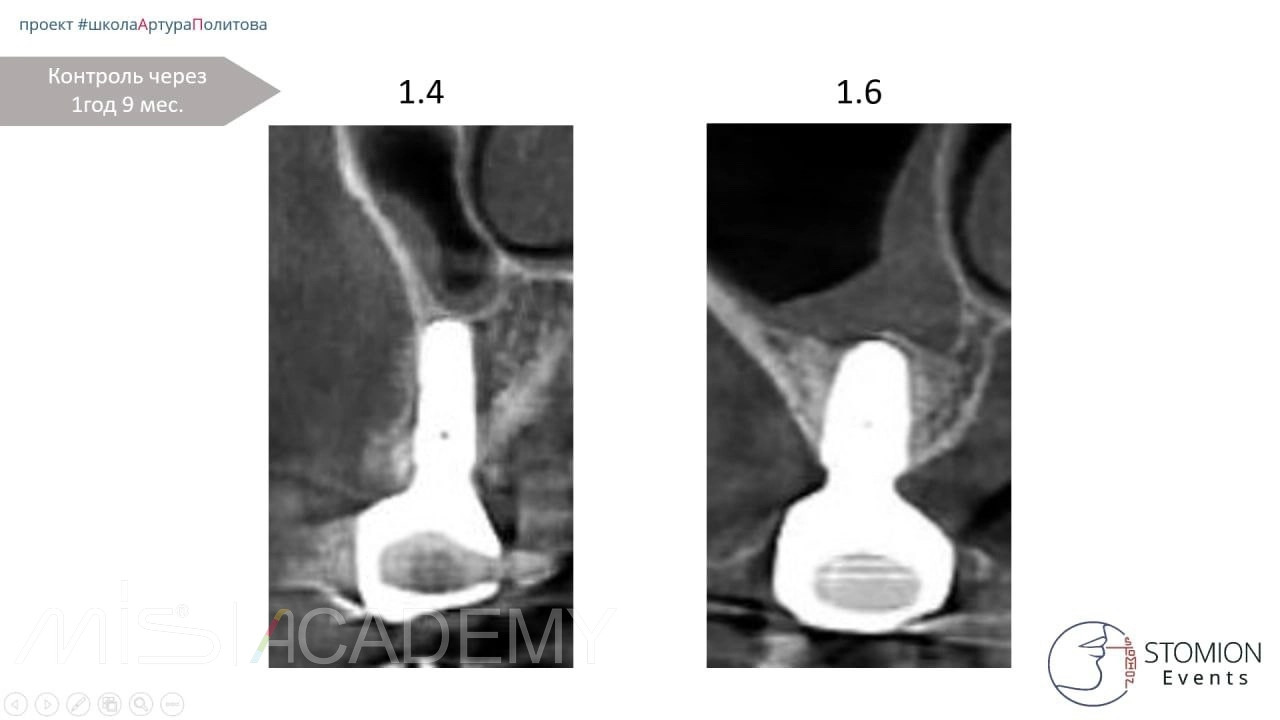

Контрольное обследование:

Через 21 месяц проведено контрольное КЛКТ-исследование. На снимках визуализируется усадка остеопластического материала над верхушкой имплантата, что связано с его аваскулярностью (отсутствием кровоснабжения).